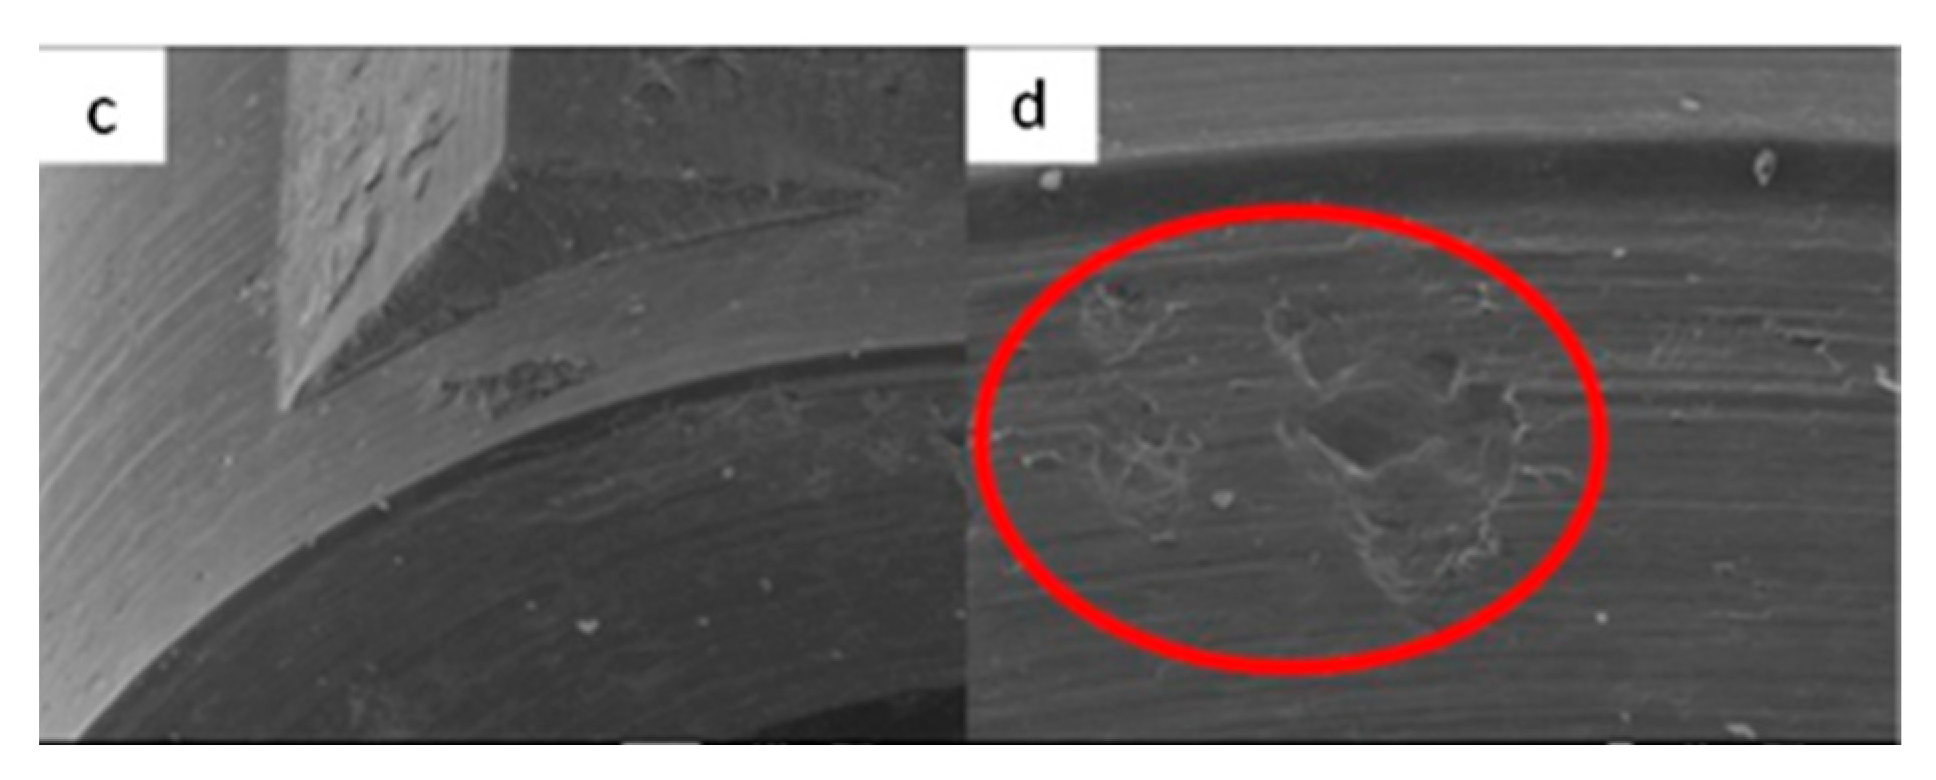

3.1.1. KL Implants

3.1.2. Essential Implants

3.1.3. SK2 Implants

3.1.4. Vega Implants

4.1. SEM Evaluation